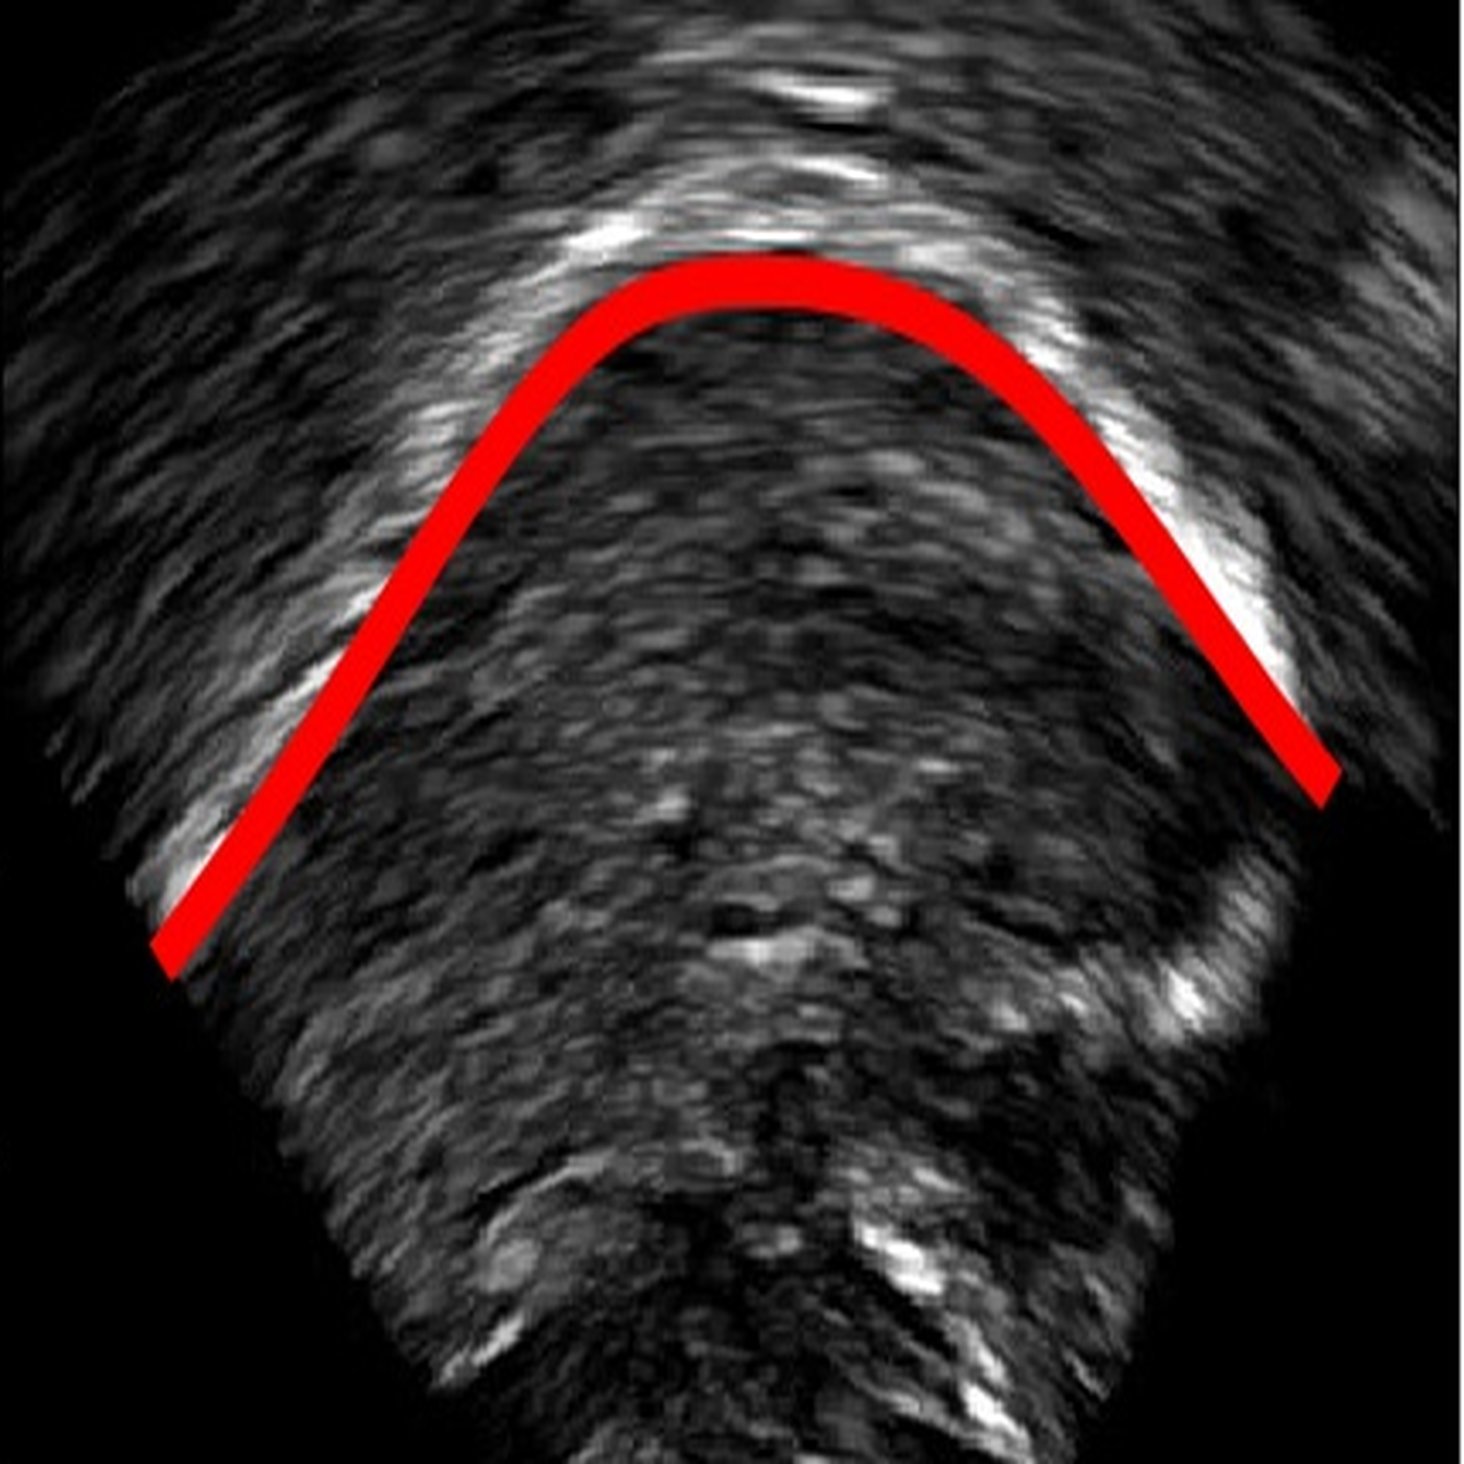

4.1 Post-processing

For each new image fed into the model, the output is a probability heatmap having the same size as the input image, with the intensity of each pixel again corresponding to the probability that the pixel is part of the tongue. A 50% threshold is then applied to the image to filter out unlikely predictions. Then a skeletonization algorithm [26] is used to reduce the white edge to a single pixel wide representation. It is then interpolated and smoothed using 'UnivariateSpline' in the SciPy Package with the default settings. The resulting output is a 100-point Cartesian coordinate representation of the predicted tongue shape.

6 Error analysis

As the CNN is trained to identify the white edges directly corresponding to the tongue surface, additional or missing white edges due to bad image quality or speaker physiology can lead to failures in identifying parts of the tongue surface. In the absence of prior knowledge of plausible tongue shapes, the model will sometimes generate tracking errors when the white edge becomes blurry or interrupted. Similarly, bright edges in the image background are likely to be recognized as part of the tongue; tongue contours generated from image frames with these edges will likely suffer from implausible curvatures as interpolation in post-processing attempts to connect these regions. There some potential solutions to these problems, including incorporating temporal constraints on tongue contour variations across frames [3], or adding a smooth constraints that penalizes discontinuity of tongue contours, or introducing a strong prior probability of possible tongue locations. In data processing, these issues can also be mitigated by tuning the parameters in post-processing to match the needs of the specific dataset, and remaining errors can also be addressed through manual correction (as even then, the workload is considerably reduced relative to manually labeling all frames).